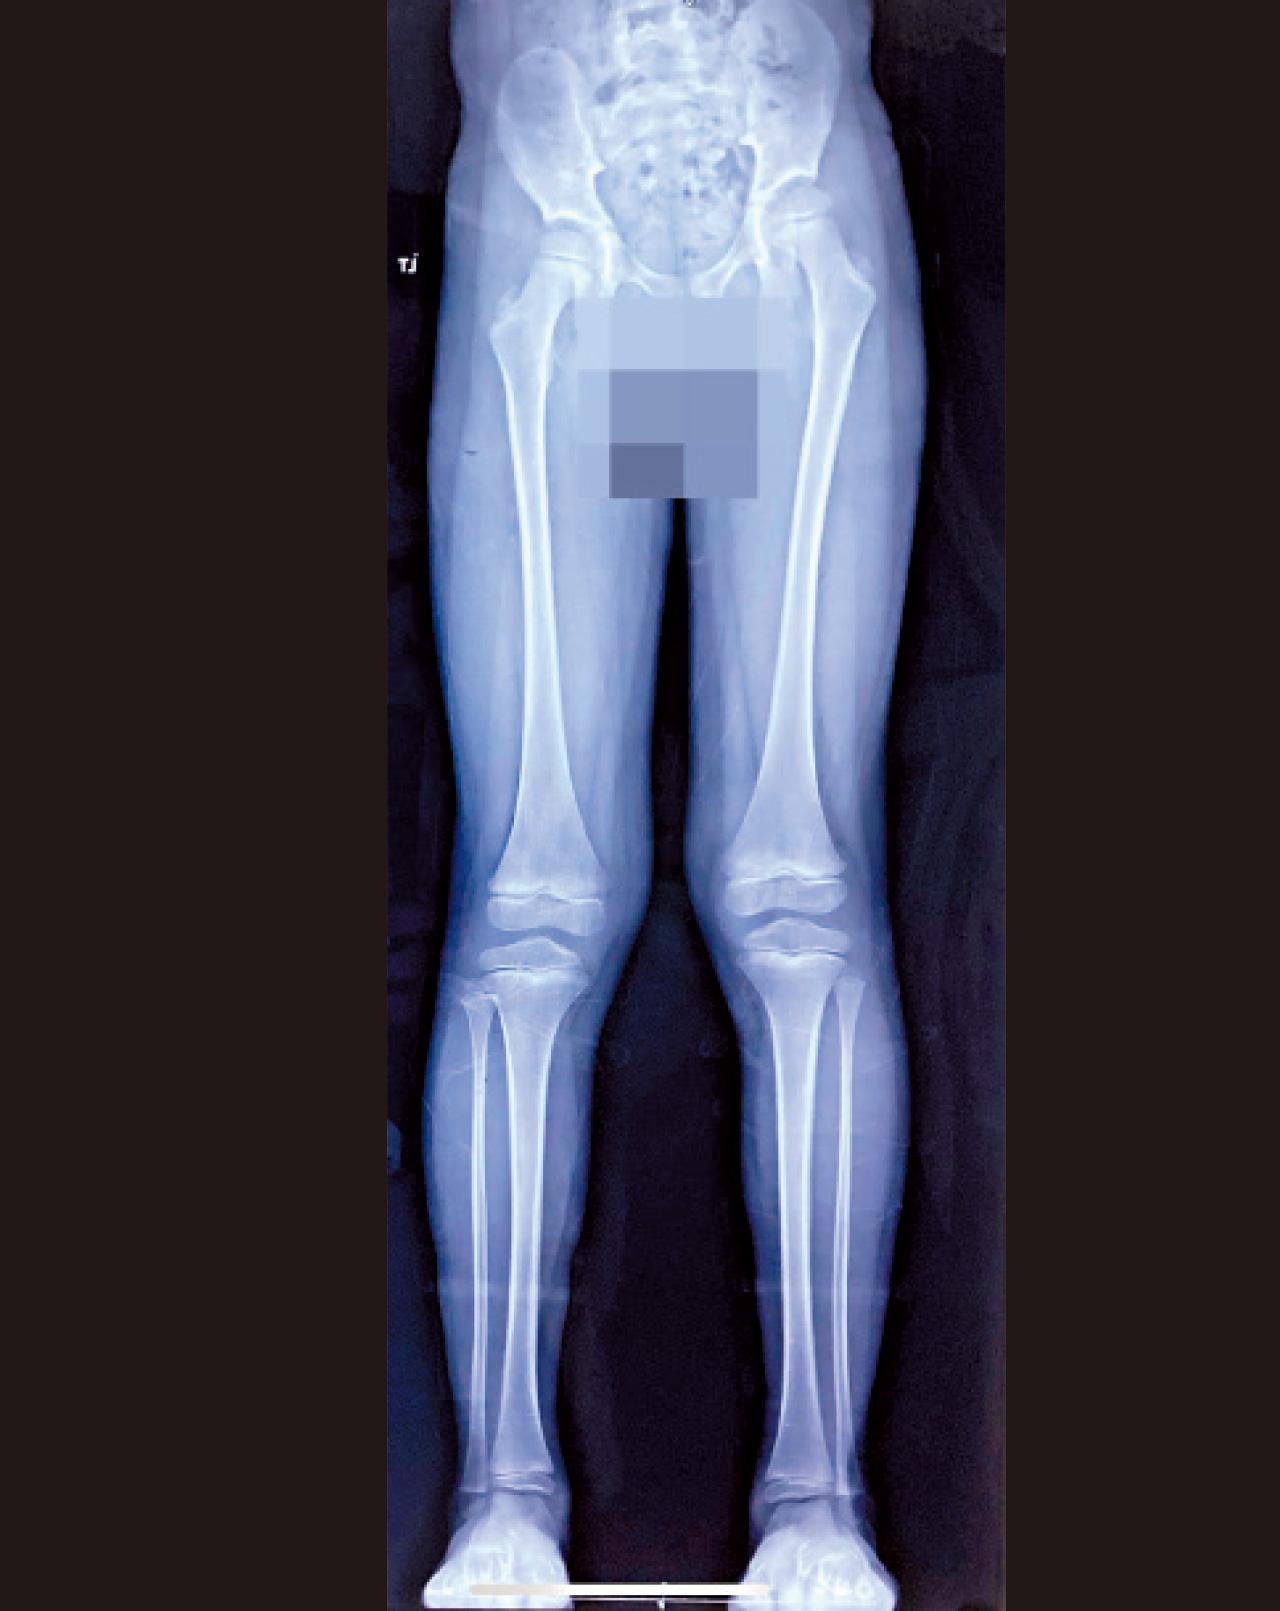

不再被長短腳困擾

長短腳是指一條腿比另一條腿長或短的情況,脊骨神經科醫生黎思駿表示,長短腳通常是由於發育、創傷等原因導致長度差異,約有10%至20%的人有不同程度的腿部長度差異。曾有田徑運動員,因家長在子女發育時期未有察覺到長短腳的問題,導致跑步時下腰椎創傷及勞損;經脊醫治療後,患者亦須長期穿著訂做的高低鞋墊彌補長短腳的差別。

長短腳問題大多因兒時下肢受創傷或發育不良引起的。下肢受創後,骨骼修復過程可能出現差異,甚至影響日後發育,令腿部長度出現變化,造成長短腳問題。而下肢發育不良亦可構成長短腳,所以要確保良好的肌肉發展及脊骨位置的排列,減低長短腳風險。

研究調查中發現,長短腳不但會造成下背疼痛,更可引發髖關節炎、壓力性骨折、髖關節鬆動、站姿平衡能力降低、髖關節的力量傳遞系統異常及運動產生傷害等,不容忽視。至於左右腳要差多少公分才足以產生不良影響?研究指出,雙腳差距1公分以上在臨床上被判定為顯著長短腳差異。黎思駿續指,長短腳主要分為結構性和功能性,前者指腿部骨骼本身有長短的差異,通常難以單靠手法治療及運動改善;功能性長短腳則指盆骨排列或下肢肌肉不相稱,大多由後天壞習慣形成,例如不良的生活習慣造成姿勢異常,運動姿勢不對導致脊椎或盆骨發生錯位等,亦是較常見的一種。

長短腳可能發生在青少年發育期間或成年期(外在因素)。家長如發現成長期的孩童左右腳實際差異大於2公分以上,建議尋求專業意見及作詳細的全脊評估。成年期的功能性長短腳可能伴隨疼痛,若發現症狀則建議及早就醫接受治療以避免情況加劇。造成功能性長短腳的原因有很多,找出功能性長短腳所造成的原因才能對症下藥,改善情況。除了解決痛症外,脊醫亦會因應情況採用不同方法調整移位的問題,也可以藉由矯形鞋墊,有效改善長短腳對患者造成的影響,故切勿耽誤治療。